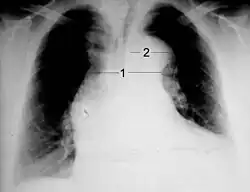

1 Mediastinum und

2 Aortenknopf

Auf einer normalen Röntgenaufnahme ist die Dissektion selbst nicht zu erkennen, indirekte Hinweise in Form einer Verbreiterung oder Doppelkontur des Mittelfells (Mediastinum) oder der Aorta können aber sichtbar sein. So ist eine Mediastinalverbreiterung bei etwa 63 % der Patienten mit einer Typ-A-Dissektion und etwa 56 % derer mit Typ-B-Dissektion nachweisbar. Insgesamt findet sich bei Dissektionsverdacht in 60–90 % der Röntgenaufnahmen irgendein auffälliger Befund, das Fehlen eines solchen Befundes schließt jedoch eine Dissektion keineswegs aus.